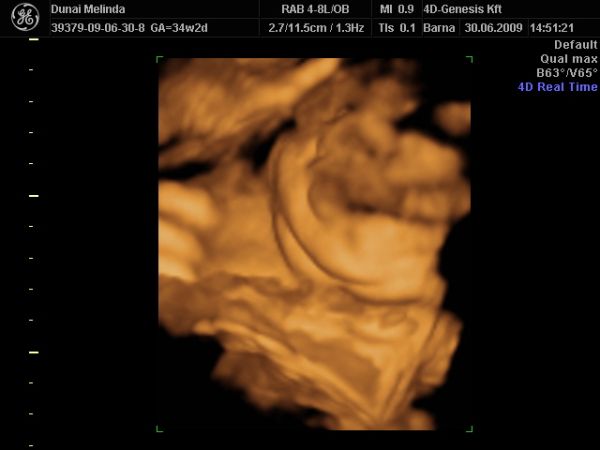

Na akkor megmutatom azt a tekintélyes tokát. Remélem Ti, mint szakavatott szemek, ki tudjátok venni a képen...

Kép